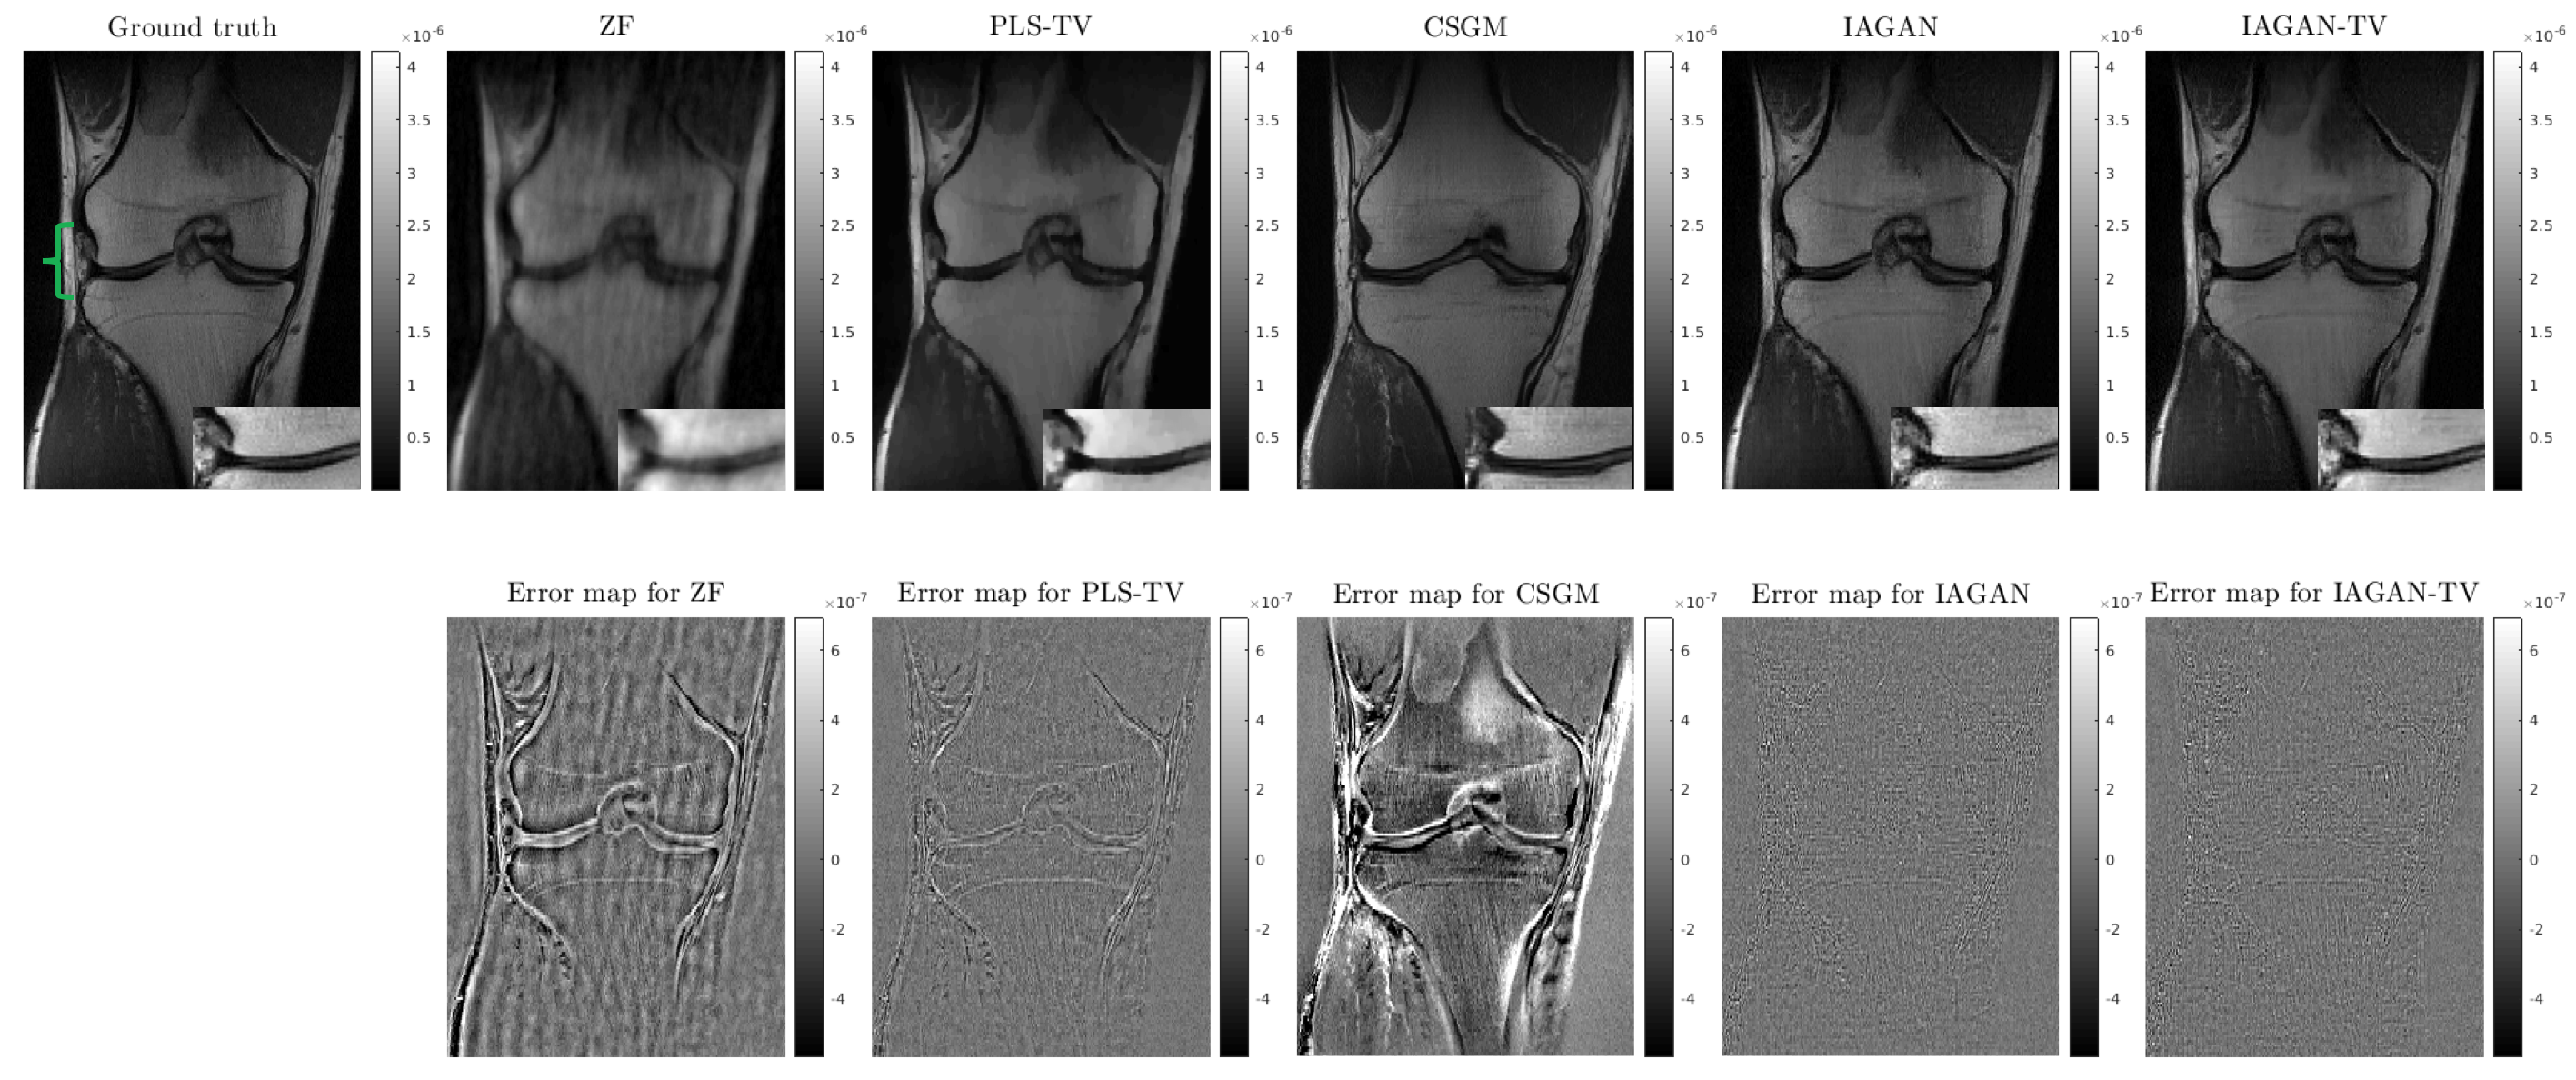

Images reconstructed by use of the IAGAN and the IAGAN-TV methods are compared with the baseline PLS-TV algorithm as well as the CSGM method in Fig. 4.

Refer to caption

Figure 4: (Top row) from left to right: Ground truth, ZF reconstruction, PLS-TV reconstruction, CSGM reconstruction, IAGAN reconstruction and IAGAN-TV reconstruction. The meniscular region indicated by the green bracket in the ground truth image is expanded for each reconstruction result at the bottom right corner of each image. (Bottom row) from left to right: Error maps for ZF, PLS-TV, CSGM, IAGAN and IAGAN-TV reconstructions respectively.

From the results, it can be observed that the IAGAN reconstruction contains fine details in regions that are of potential interest for medical diagnosis and retains the bone texture to a large degree, as compared with the PLS-TV method where these relevant features could not be reliably recovered. This can be further highlighted with an expanded view of the lateral meniscus for each reconstructed image. Radiologists rely on a clear view of the meniscular region in order to detect tears in the knee [19]. However, it can be observed that the meniscus appears oversmoothed in the PLS-TV reconstruction, while for the IAGAN reconstruction, it remains sharp with discernible fine features. On the other hand, the image produced by the CSGM method contains detailed features and texture information similar to knee images in the training data, but lacks fidelity with the observed measurements. The IAGAN-TV reconstruction regularizes the IAGAN solution and can remove some of the grain-like artifacts that may appear due to data incompleteness. The error maps with respect to the ground truth further illustrate the points above.